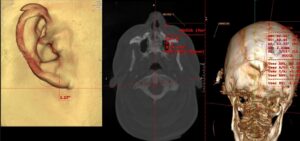

Why Vertigo and Dizziness Often Come From the Neck

Table of Contents Toggle Why Vertigo and Dizziness Often Come From the Neck — Not Just the Inner EarVertigo Isn’t Always an Inner Ear IssueCervicogenic Dizziness: A Neck-Related Form of…

Dizziness That Won’t Go Away

Table of Contents Toggle Dizziness That Won’t Go Away? The Upper Cervical Spine May Be the Missing LinkWhen Dizziness Isn’t Just an Inner Ear ProblemThe Cranio-Cervical Junction: Where Structure Meets…